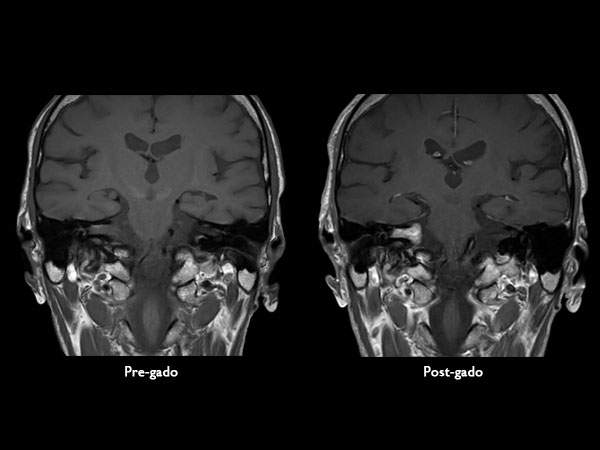

IAC – Acoustic Neuroma

Decreasing hearing of the right side. Buzzing and beating sensation in the right ear. Sometimes pain. Request for MRI of the inner ear without and with contrast agent.